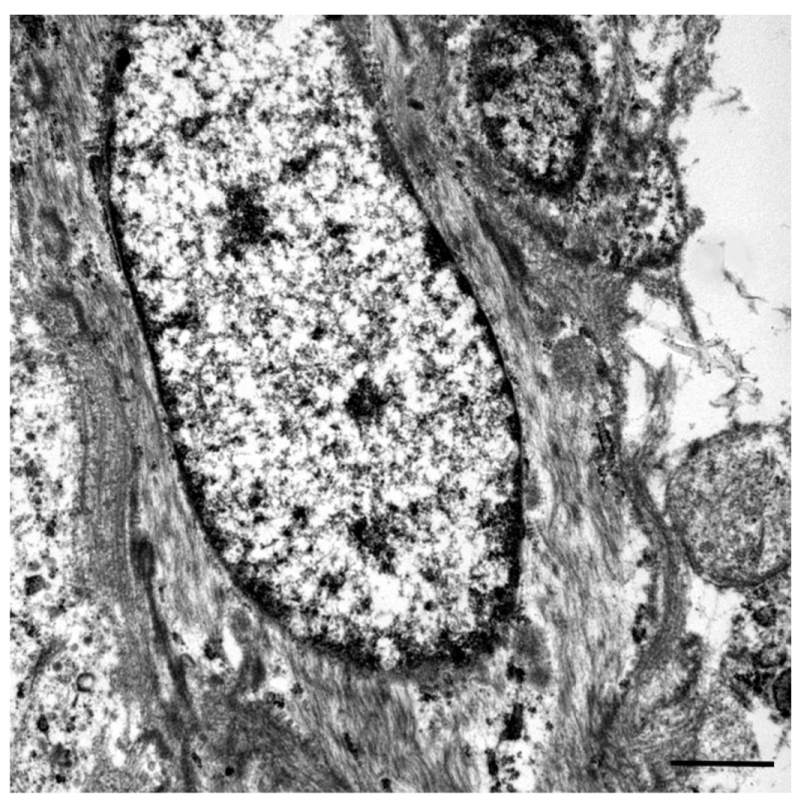

2. Case Presentation